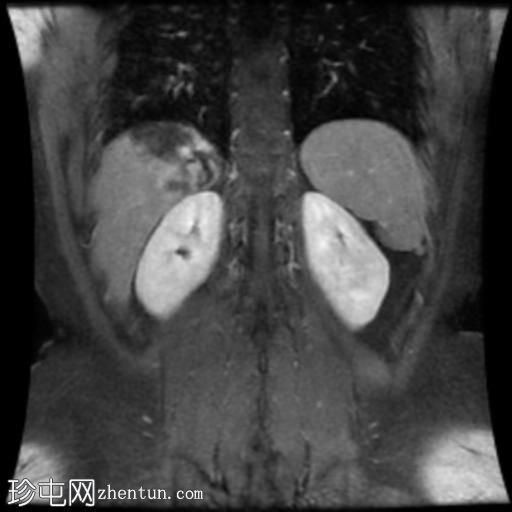

冠状位T1加权像增强扫描

肝脏第7段可见一边界清晰的分叶状肿块。T1加权像呈低信号,T2/T2脂肪抑制序列呈高信号,动脉期呈不连续结节状周边强化,门静脉期呈向心性强化,延迟期完全强化。DWI序列呈高信号,ADC值呈混合信号。